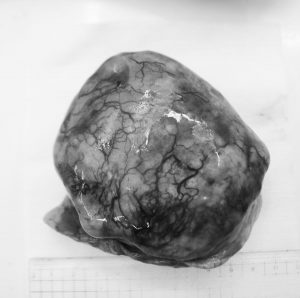

手術により腫瘍を摘出しました。

右側肋骨と肋骨の間を切開し、腫瘍を摘出しました。

病理検査の結果悪性腫瘍の肺腺癌でした。